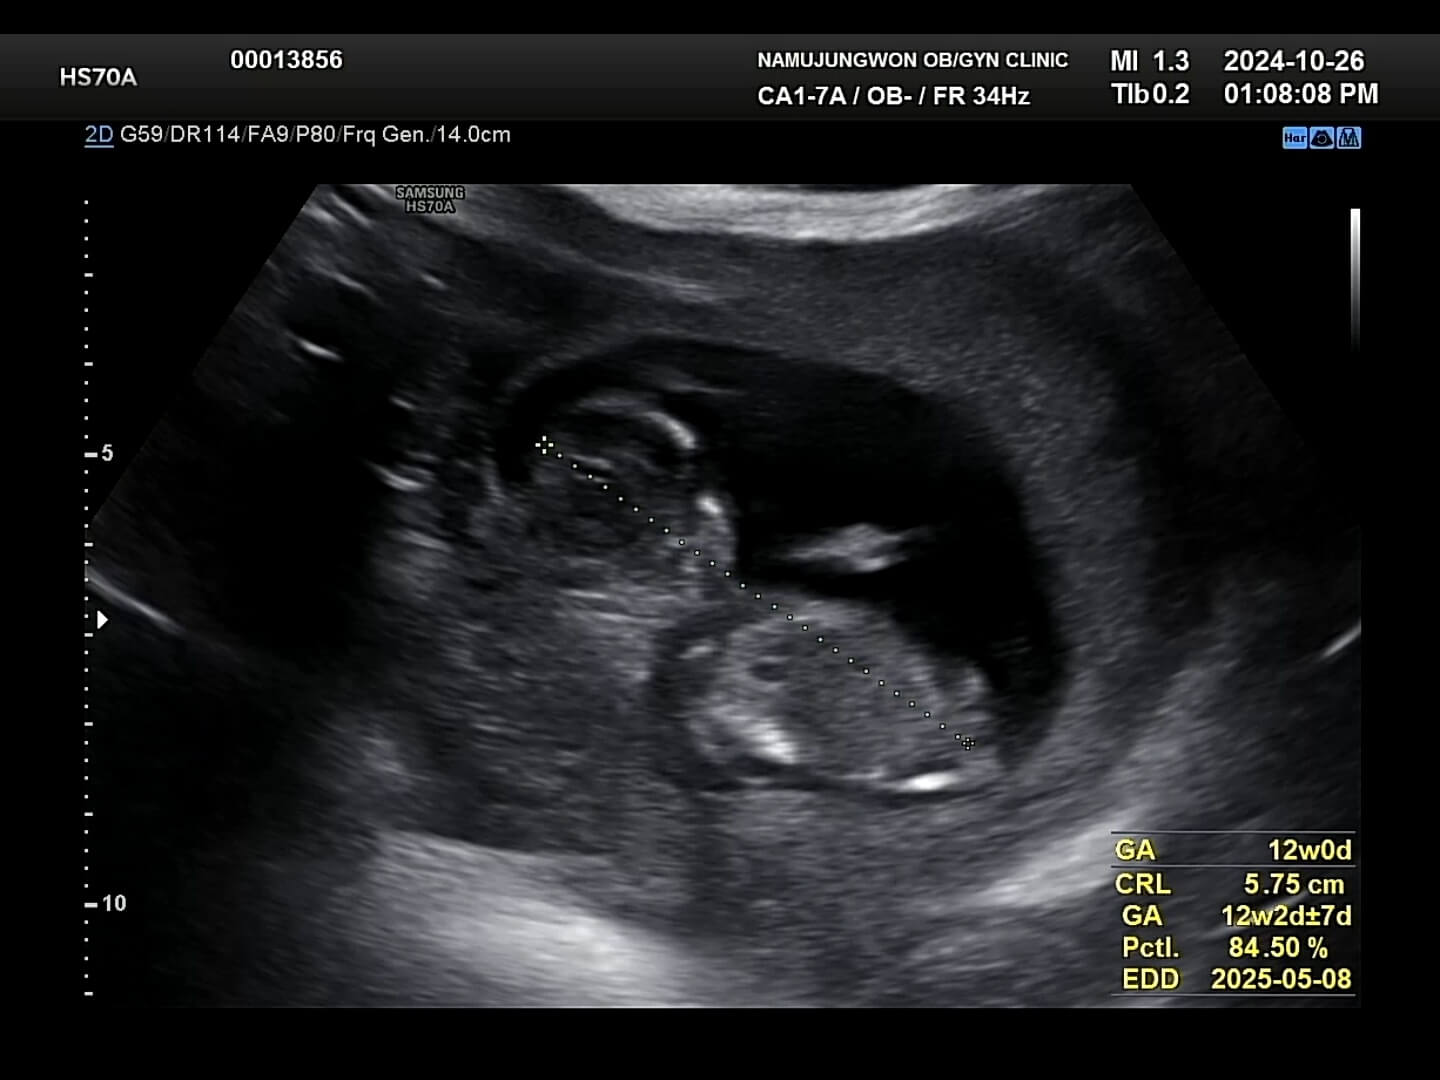

5. 1차 기형아 검사와 성별 확인

이제 일반 초음파로 목투명대와 코뼈가 잘 형성되었는지 확인합니다. 목투명대는 이물질이 쌓이는 공간이라고 보시면 되고, 이 목투명대가 2.5~3mm 정도 이상되면 기형아 확률이 높아지기에 이때, 융모막 검사나 니프티 검사를 실시하게 됩니다.

목투명대-코뼈 꾸미 목투명대는 다행이 1mm로 통과하였고, 오른쪽 사진을 보시면 얼굴 쪽에 하얀색깔 뼈가 있는데 이게 코뼈라고 하시더라구요. 이 코뼈도 잘 형성되어 있어서 눈으로 확인해주시는 1차적인 검사는 통과했어요. 그리고 나서 피를 뽑았는데요. 12주에 1차 기형아 검사로 피를 뽑고, 16주쯤에 2차 기형아 검사로 피를 또 뽑는데, 이 두 시기에 뽑은 피를 검사해서 최종적으로 기형아 검사 '저위험군'인지 '고위험군'인지 확인이 됩니다. 꾸미는 목투명대와 코뼈가 잘 보여서 일반 기형아검사를 실시하였습니다.

아, 그리고 성별은 원장님께서 80% '블루'라고 보시면 될 것 같아요. 라고 말씀해주셨는데 과연 반전이 일어날까요?